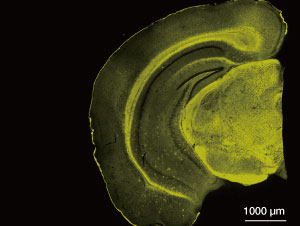

The fluorescent probe, BD-Oligo, developed by A*STAR detects amyloid-beta oligomers (yellow) in an Alzheimer’s disease-affected brain.

© 2016 A*STAR Singapore Bioimaging Consortium

After testing 3,500 DOFL compounds, they found BoDipy-Oligomer, known as ‘BD-Oligo’. This showed a stronger response to amyloid-beta oligomers, with the signal decreasing once a polymer started to form, which demonstrated to Chang and the team that they had found the first ever selective probe for oligomers.

With this fluorescent probe, the team was able to monitor oligomers in real time during the formation of fibrils. Additionally, in vivo tests on live mice revealed that BD-Oligo was able to cross the blood-brain barrier without any apparent toxicity.